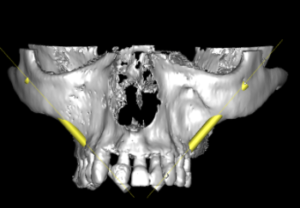

Implantes zigomáticos

Paciente con atrofia total del maxilar, resuelta con Implantes ZIGOMÁTICOS y 1 implante anterior. Planificación informática y Modelos 3D

Imagen de la rx con los implantes colocados, e imagen de la prótesis acrílica.

Implantes zigomáticos

Paciente con atrofia maxilar total, resuelta con la colocación de 4 implantes zigomáticos. . La prótesis definitiva ha sido realizada en metal-cerámica.

Planificación informática y modelos 3D

Implantes zigomáticos

Atrofia maxilar total, resuelta con la colocación de 2 implantes zigomáticos y 2 implantes anteriores . Planificación informática y modelos 3D.

Foto de la planificación digital del caso